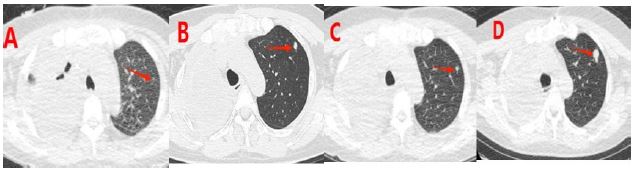

Figure 3: (A-D) show chest CT images at 1 month, 2 months, 3 months, and 6 months after surgery, respectively. It can be seen that the nodule in the upper lobe of the left lung gradually increases.